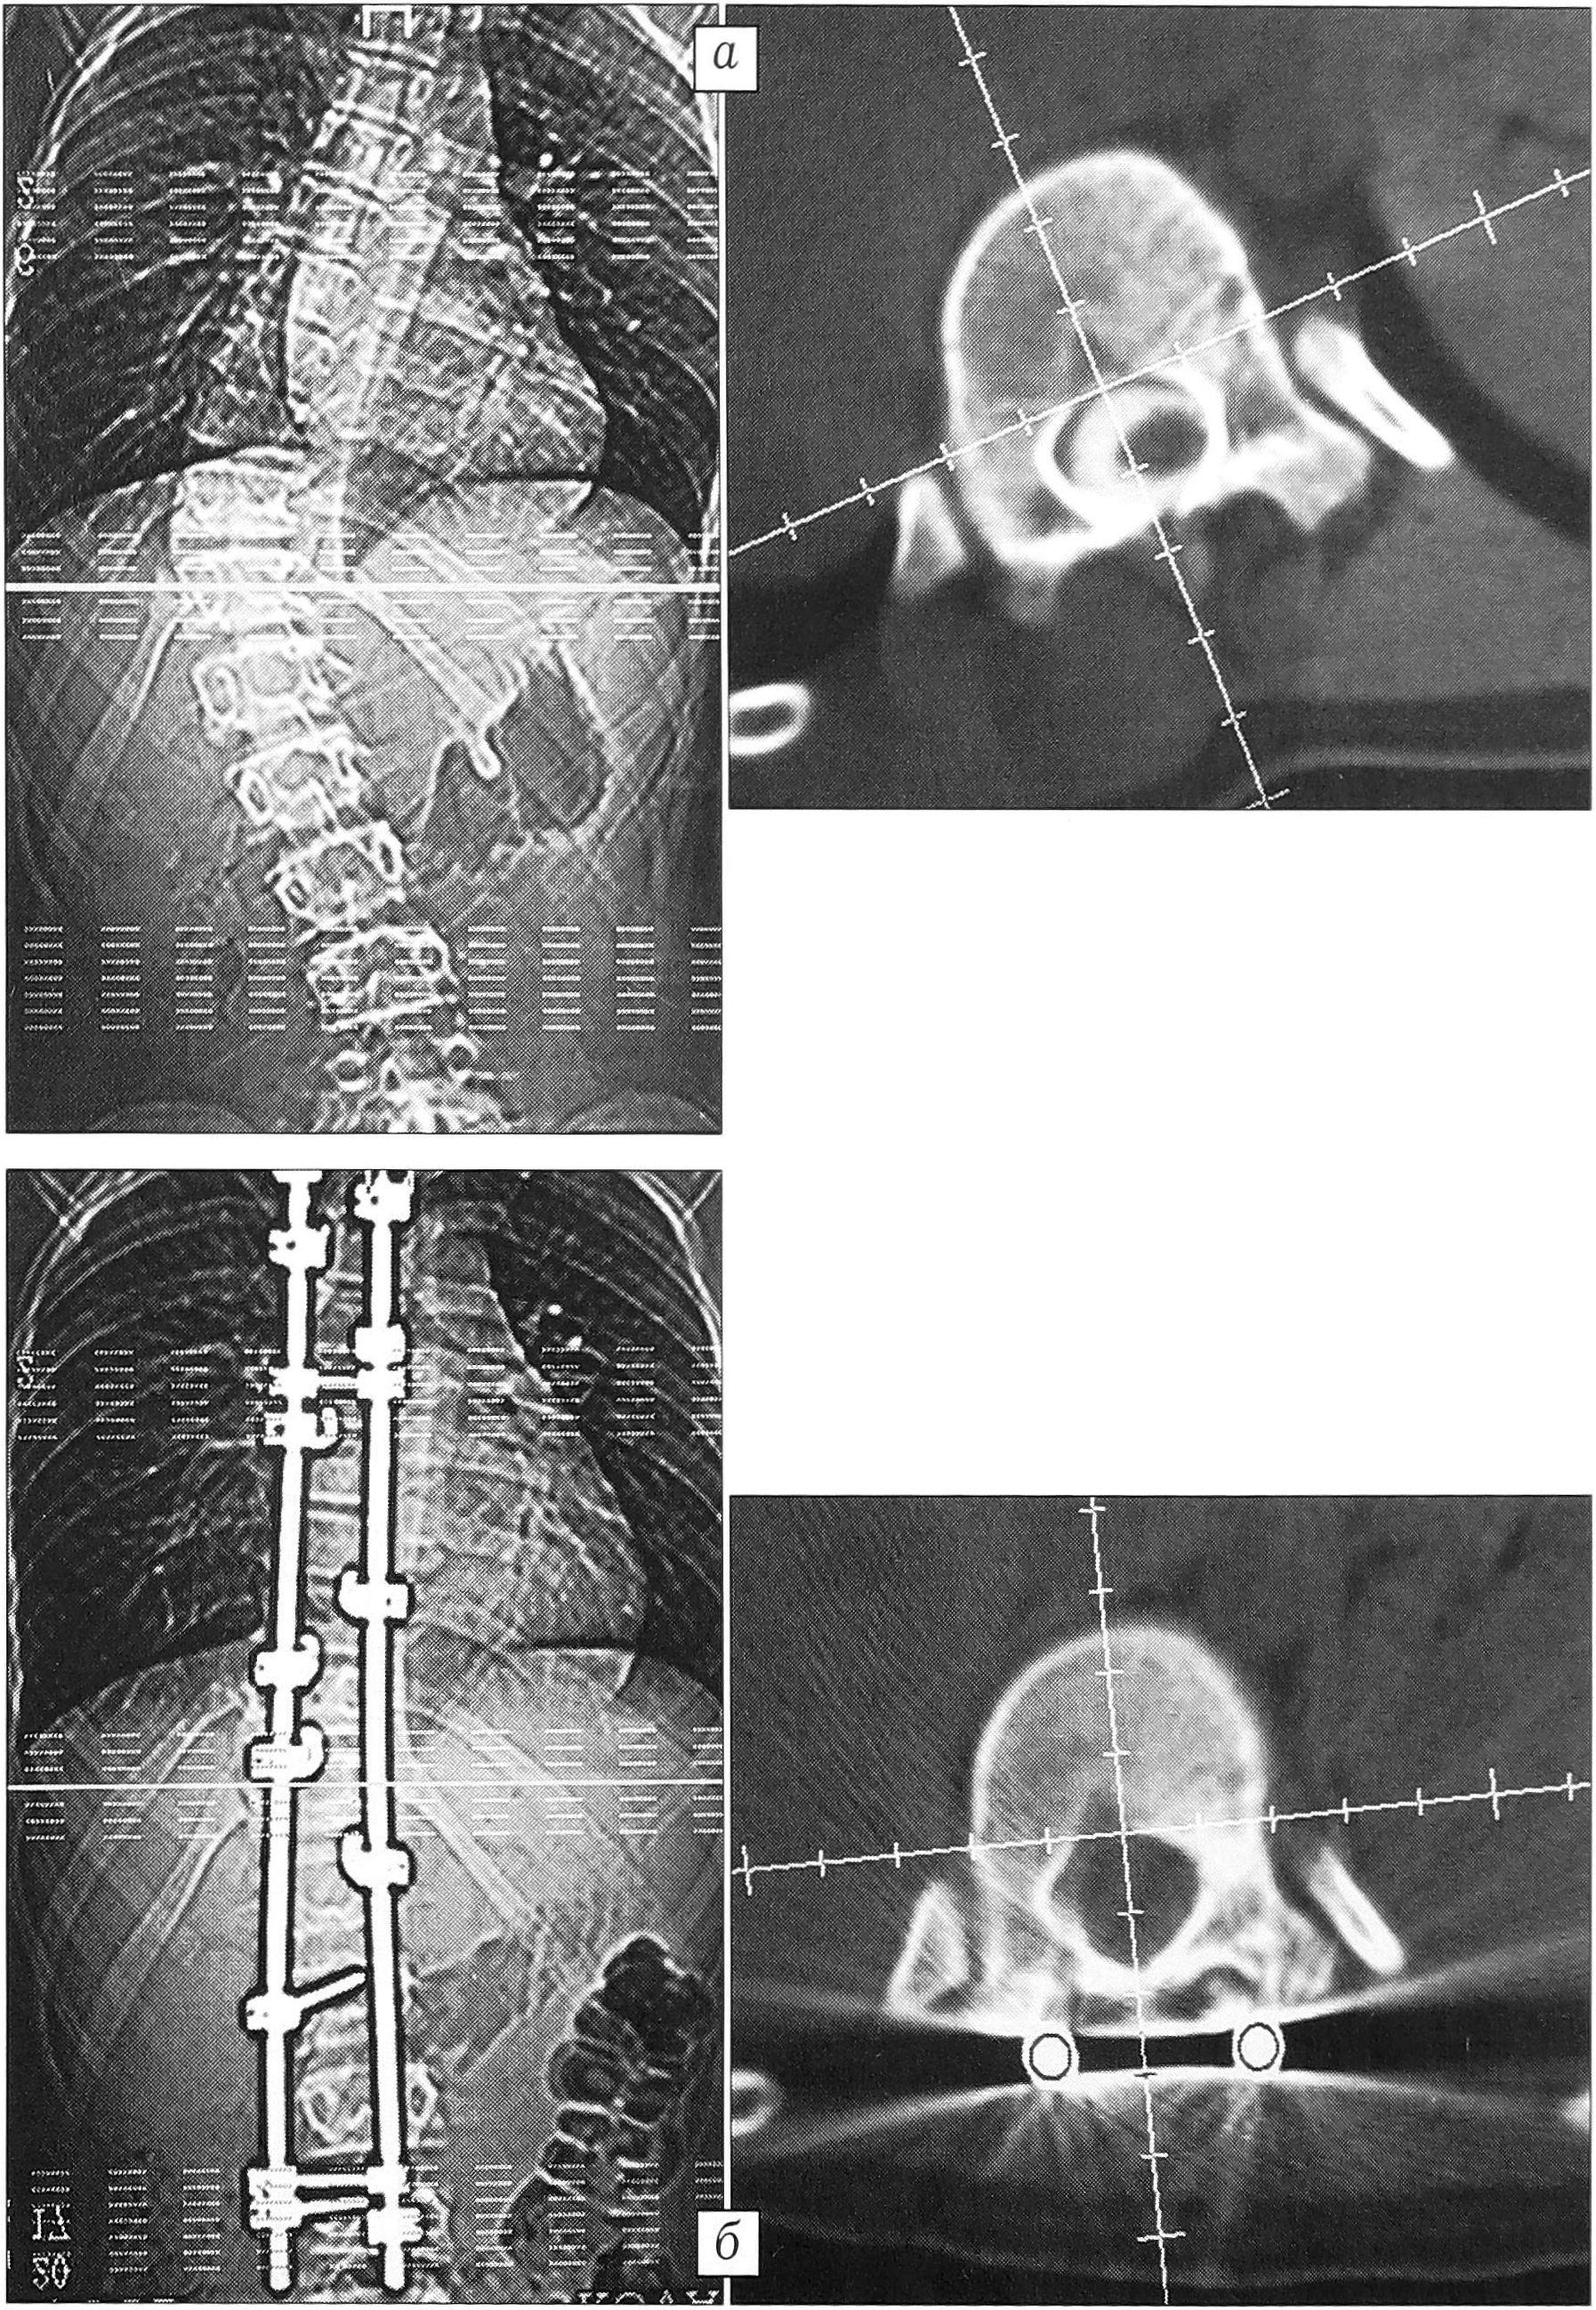

Среднее абсолютное значение ротации, измеренной в горизонтальной плоскости, до оперативного лечения составило 24,5° (в группе больных с углом менее 80° оно равнялось 22,36°, с углом более 79° составляло 30,75°). Максимальное значение ротации, равное 45°, выявлено у больного А. с левосторонним грудным сколиозом с максимальной в исследуемой группе величиной общего угла основной дуги — 128° (рис. 3). После оперативного лечения среднее абсолютное значение ротации, измеренной в горизонтальной плоскости, составило 21,5° (19,5° у больных с углом деформации менее 80° и 30,0°— с углом более 79°), т.е. разница с предоперационным значением находится в пределах ошибки метода. Максимальная деротация, равная 17° (70,8%), получена у пациентки К. с диспластическим правосторонним грудным сколиозом. Существенная величина деротации позволяет считать ее истинной (рис. 4).

Рис. 4. КТ больной К. с правосторонним грудным сколиозом до (а) и после (б) оперативного лечения. Деротация вершинного позвонка 17° (70,8%).

Нотация вершинного позвонка, измеренная относительно верхнего нейтрального, до операции равнялась в среднем 24,85°, т.е. была сравнима с абсолютной. После оперативного лечения она составила 18° — разница 6,85° (27,56%), что несколько больше соответствующего абсолютного показателя. В целом полученная коррекция ротации у каждого пациента несколько больше, поскольку верхний нейтральный позвонок, относительно которого проводятся измерения, также меняет свое положение в пространстве. В одном случае абсолютная деротация вершинного позвонка составила 5° (19%), а относительная — 11° (48,8%), что было связано с увеличением ротации вершинного позвонка на 6° (рис. 5).